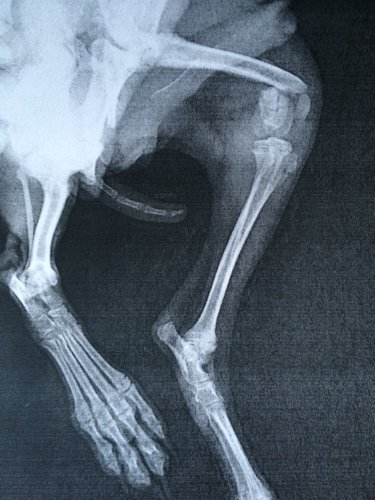

五个月小狗腿被踩断了,去了医院说这个位置要做内固定,手术成功率为一半,而且还要打全麻醉也有风险,到

五个月小狗腿被踩断了,去了医院说这个位置要做内固定,手术成功率为一半,而且还要打全麻醉也有风险,到底咋办呢?还有没有别的办法?知道的回答,谢了!

你好,看片子可确定是股骨远端骨折,这个位置只能安径院进行内细挤固定治疗,其它外固定等保守治团禁疗效果都不好。